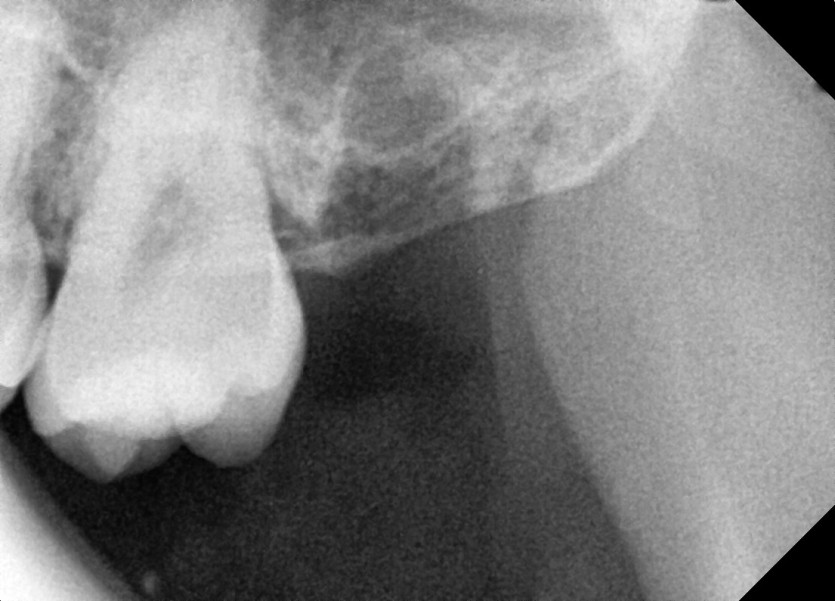

#28,38 사랑니 발치

구강외과 전문의가 당일 발치했습니다.